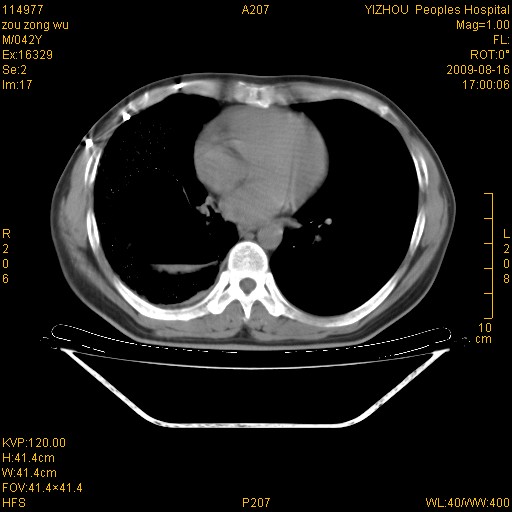

以下是引用zjzjr在2009-8-17 10:42:00的发言:[br]右侧间质性肺炎伴纤维化,右肺下叶肺囊肿伴感染(不除外外伤后引起),右肺野及胸壁软组织\\肝内见多发斑点状,中枪了吧.右侧胸膜肥厚\\粘连.